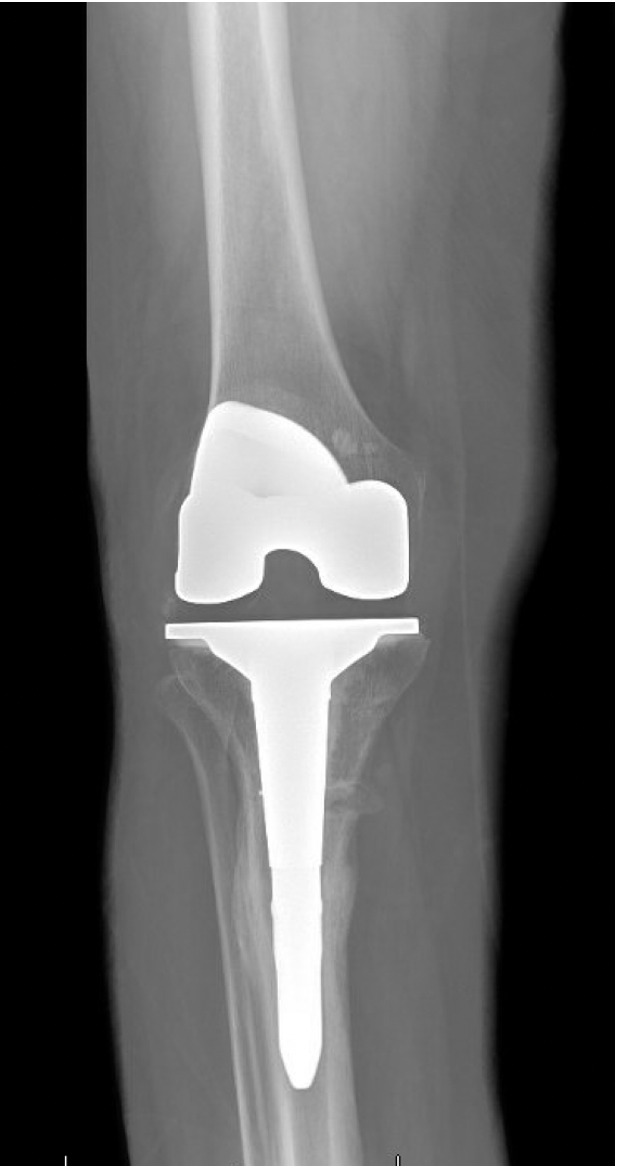

Quantitative range-of-motion and outcome-score data are summarized in Table 1. At the two-week clinic visit the incision was fully healed and sutures were removed. The patient continued full weight bearing in the brace. By six weeks the osteotomy displayed bridging callus across the osteotomy site (Figure 6), the brace was discontinued, and she achieved an unrestricted gait pattern without assistive devices. Four months after surgery, the patient had resumed activities such as tennis and reported no pain or swelling. Radiographs at that time demonstrated complete cortical union without any interval changes in alignment (Figure 7). At the nine-month assessment she reported hiking up to five miles and skiing on groomed slopes without limitation. Imaging showed continued consolidation of the osteotomy and stable components (Figure 8).

Trial components were inserted and demonstrated balanced flexion and extension gaps and central patellar tracking without the need for lateral release. The tibia was subsequently punched after confirming appropriate rotation for adequate patellar tracking. Final implantation proceeded with pressurized cement for the posterior-stabilized femoral component and the tibial baseplate under tourniquet insufflation. The diaphyseal press-fit stem was again confirmed to span the osteotomy by more than two cortical diameters under fluoroscopic guidance (Figure 4). Autogenous cancellous graft harvested from the femoral chamfer cuts was tightly packed into the osteotomy gap and along the medial cortex. The patella was resurfaced with a medialized polyethylene button.